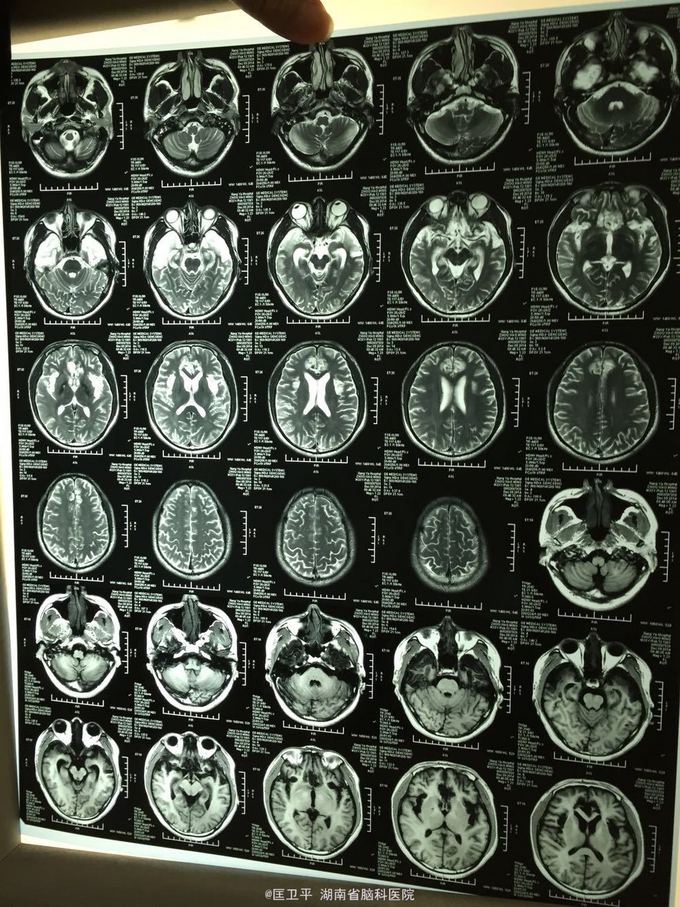

电击伤后智力低下,伤人毁物1年。 一年前在工地被电击伤昏迷,心跳呼吸停止,十几分钟后才有不规范的人工呼吸,持续约40分钟,心跳呼吸恢复。但患者智力低下,远近记忆很差,疑人害,伤人毁物严重,无法管理。

神清欠合作,五官无畸形,四肢活动正常,无神经定位体征。智能记忆很差,有被害妄想,有冲动攻击行为,无自知力,个人生活无法自理。

奥拉西坦,神经节䇞酯等护脑治疗; 丙戊酸镁、碳酸锂 稳定情绪; 奥氮平控制精神症状。 高压氧,经颅磁刺激治疗,心理治疗。

智力记忆恢复差,精神症状改善较好。